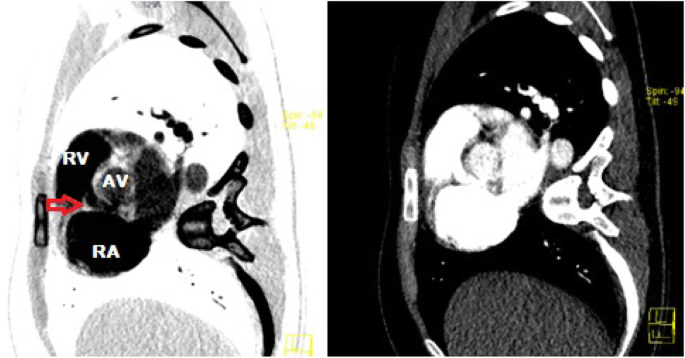

CTPA images were retrospectively reconstructed which visualised the SVA and shunt, likely originating from the right coronary sinus into the right ventricle (Fig. 5).

Since the patient had an acutely ruptured SVA, a surgical repair was proposed given significant left-to-right shunting and to prevent RV overload. She underwent open-heart surgery with excision of the aneurysm and pericardial patch repair of the right coronary cusp-SVA fistula (Fig. 6). At routine outpatient follow-up 4 weeks later, she reported no further symptoms, resolution of her cardiac murmur and successful repair on repeat transthoracic echocardiography.